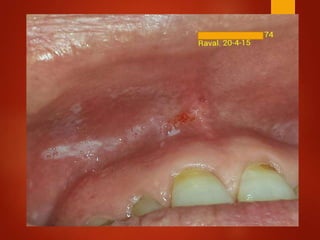

El documento es un registro médico odontológico que muestra las fechas de las visitas de un paciente al centro de salud El Raval, incluyendo exámenes y tratamientos realizados como la extracción de cálculos salivales en abril y mayo de 2012.